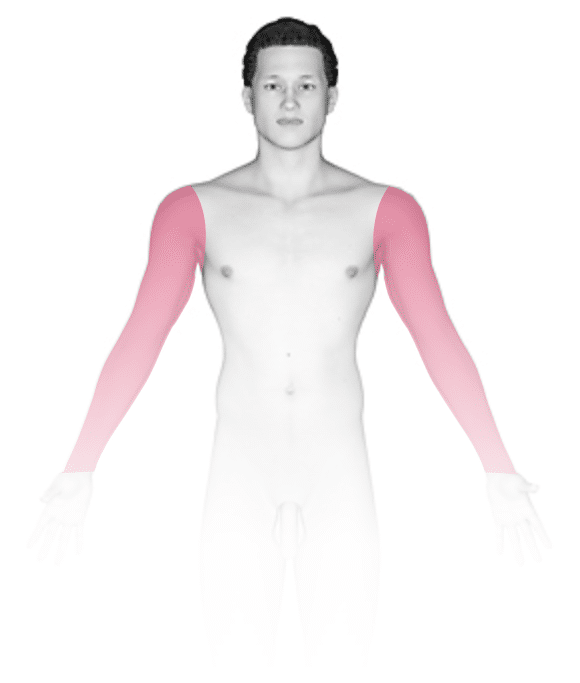

Bedsores occur at areas of abnormal pressure on the body:

- In a wheelchair, this is usually the tailbone (coccyx) or buttocks area, shoulder blades, spine, or backs of the arms or legs.

- In a bed, they may occur on the back of the head, ears, shoulder blades, hips, lower back, tailbone, or the backs or sides of the knees, elbows, ankles, or toes.